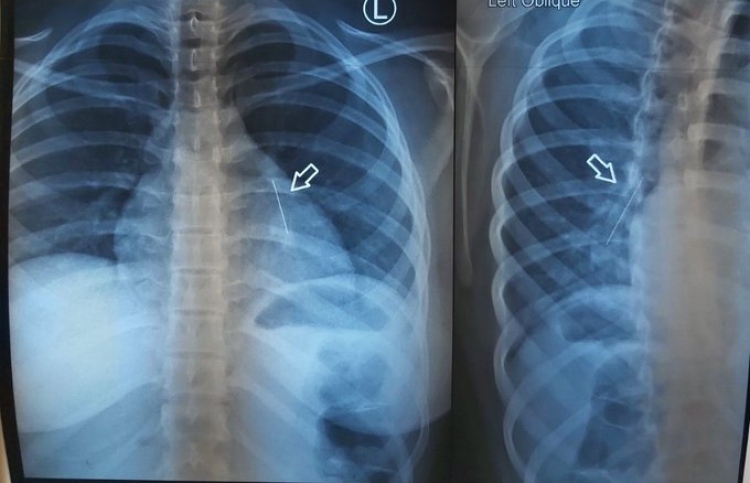

ކުޑަކުއްޖާގެ މޭގަ ތާށިވި އެތިކޮޅު އިންޑިއާއިން ނަގައިފި

ނޭވާހޮޅީގައި ކެޝޫނަޓެއް ތާށިވެ، ނުރައްކާވެއްޖެ

11 އަހަރުގެ ކުއްޖެއްގެ ފުއްޕާމެއިން ޕިނެއް ނަގައިފި